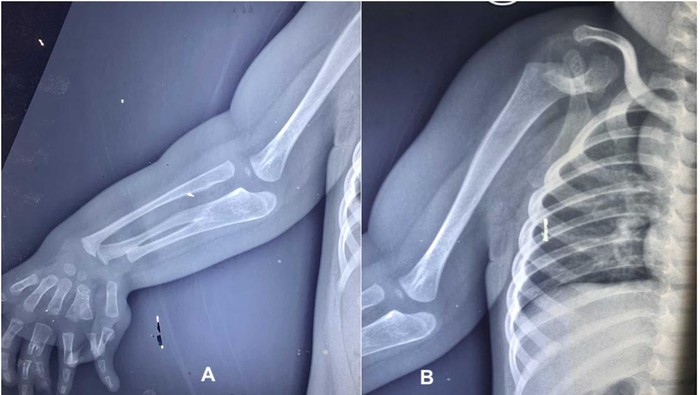

Jakarta โ Anak berusia dua tahun lahir dengan kondisi langka. Saat lahir bayi tersebut memiliki banyak jari dan tulang lengan.